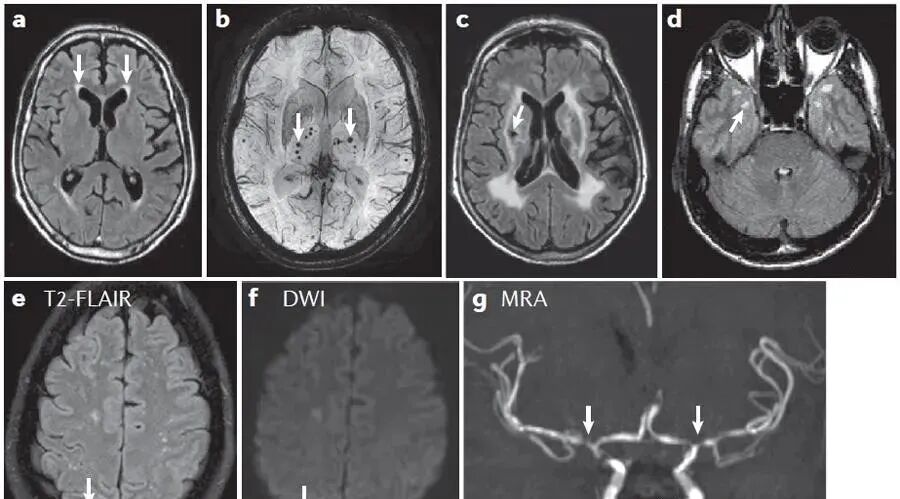

随着国内外医学影像检查的飞速发展,X光机、CT、MRI在临床工作中的广泛应用,医学影像诊断为精准医疗提供了坚实的基础,但基层医疗卫生单位医学影像工作人员的诊断水平急需提高。

(2)、X光片、CT、MRI及造影片的阅读法。

(3)、脊柱影像检查基础方法介绍和X光片判读技术。

(4)、根据影像检查结果如何判断定位脊柱相关疾病。

(5)、颈、胸、腰、骶椎,骨盆及骶髂关节的观片技巧及典型病例解析、答疑)。